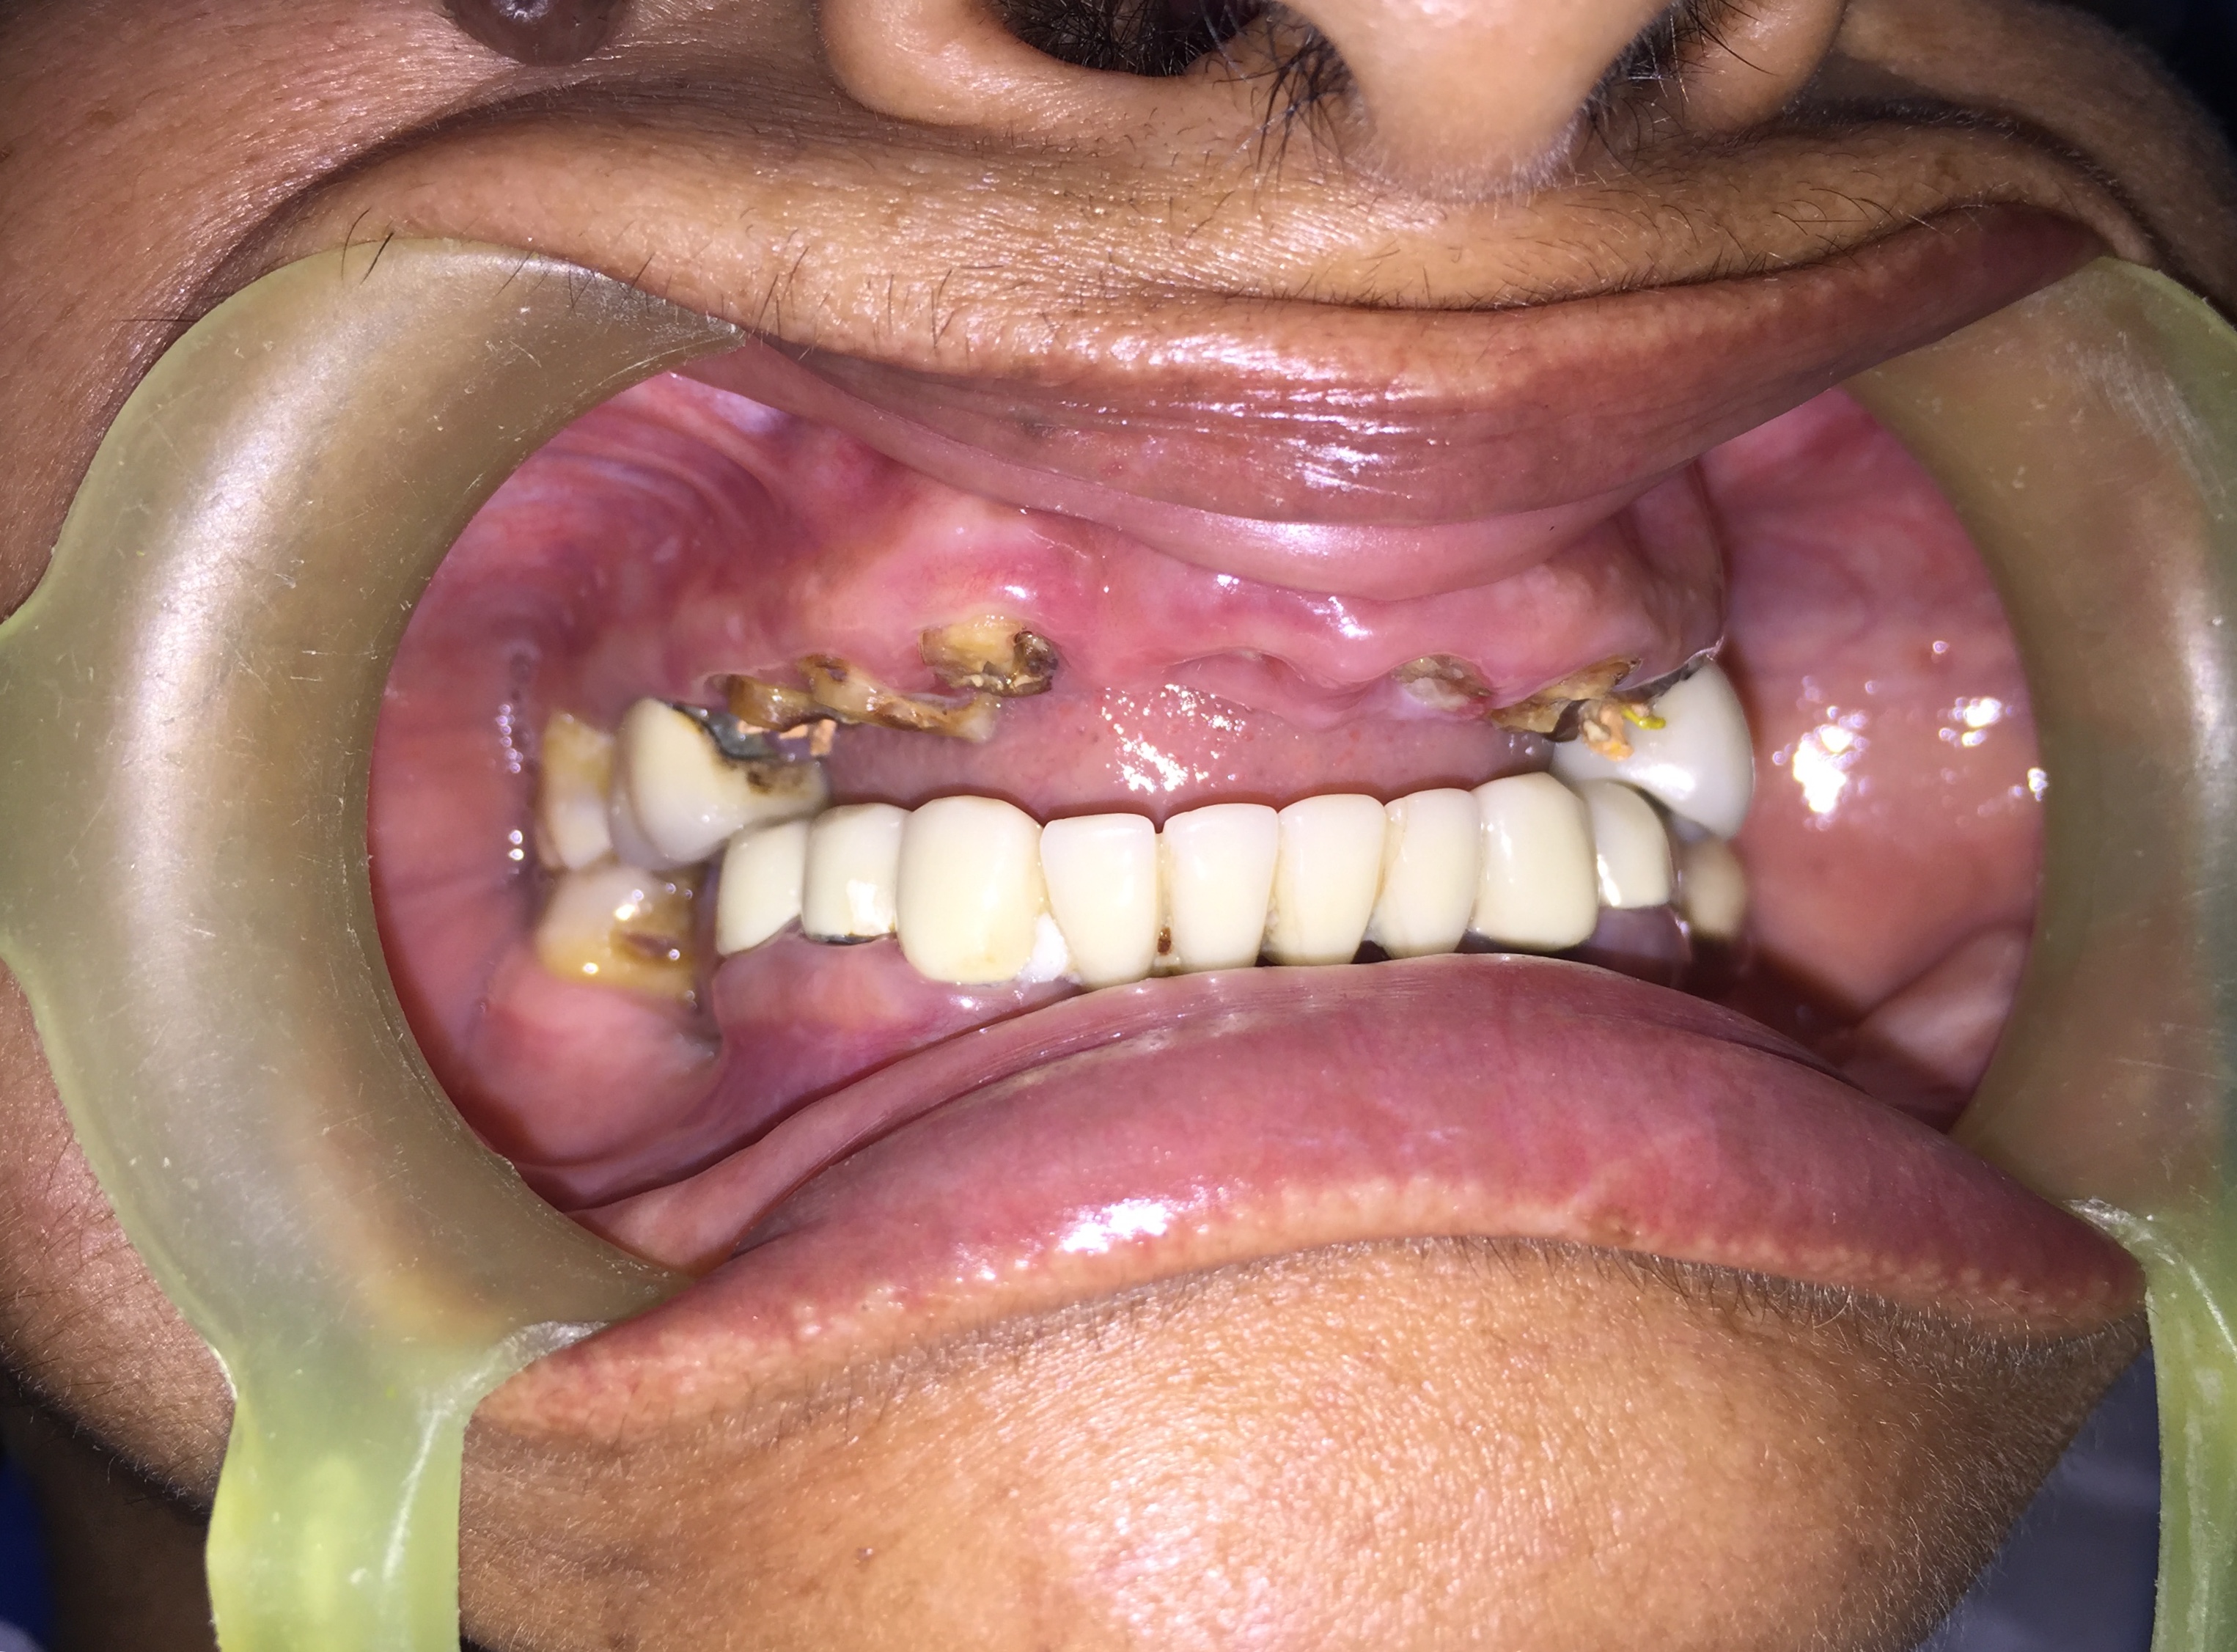

Upper Jaw Full Mouth Implants with Immediate Crowns